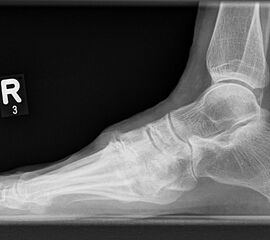

Eine Röntgenaufnahme unter Belastung mit Abbildungen des ganzen Fußes a. p. (mit 15-20° Röhrenkippung) und seitlich, sowie Schrägaufnahmen, reichen meist zur Diagnose. Manchmal ist ein MRT und DVT ergänzend hilfreich. Selten wird die Indikation für ein SPECT CT gestellt (Abb. 6).

• konventionelle Röntgenbilder mit Belastung im Stehen a. p. und seitlich, ggf. schräg (Abb. 9, 10 und 11).